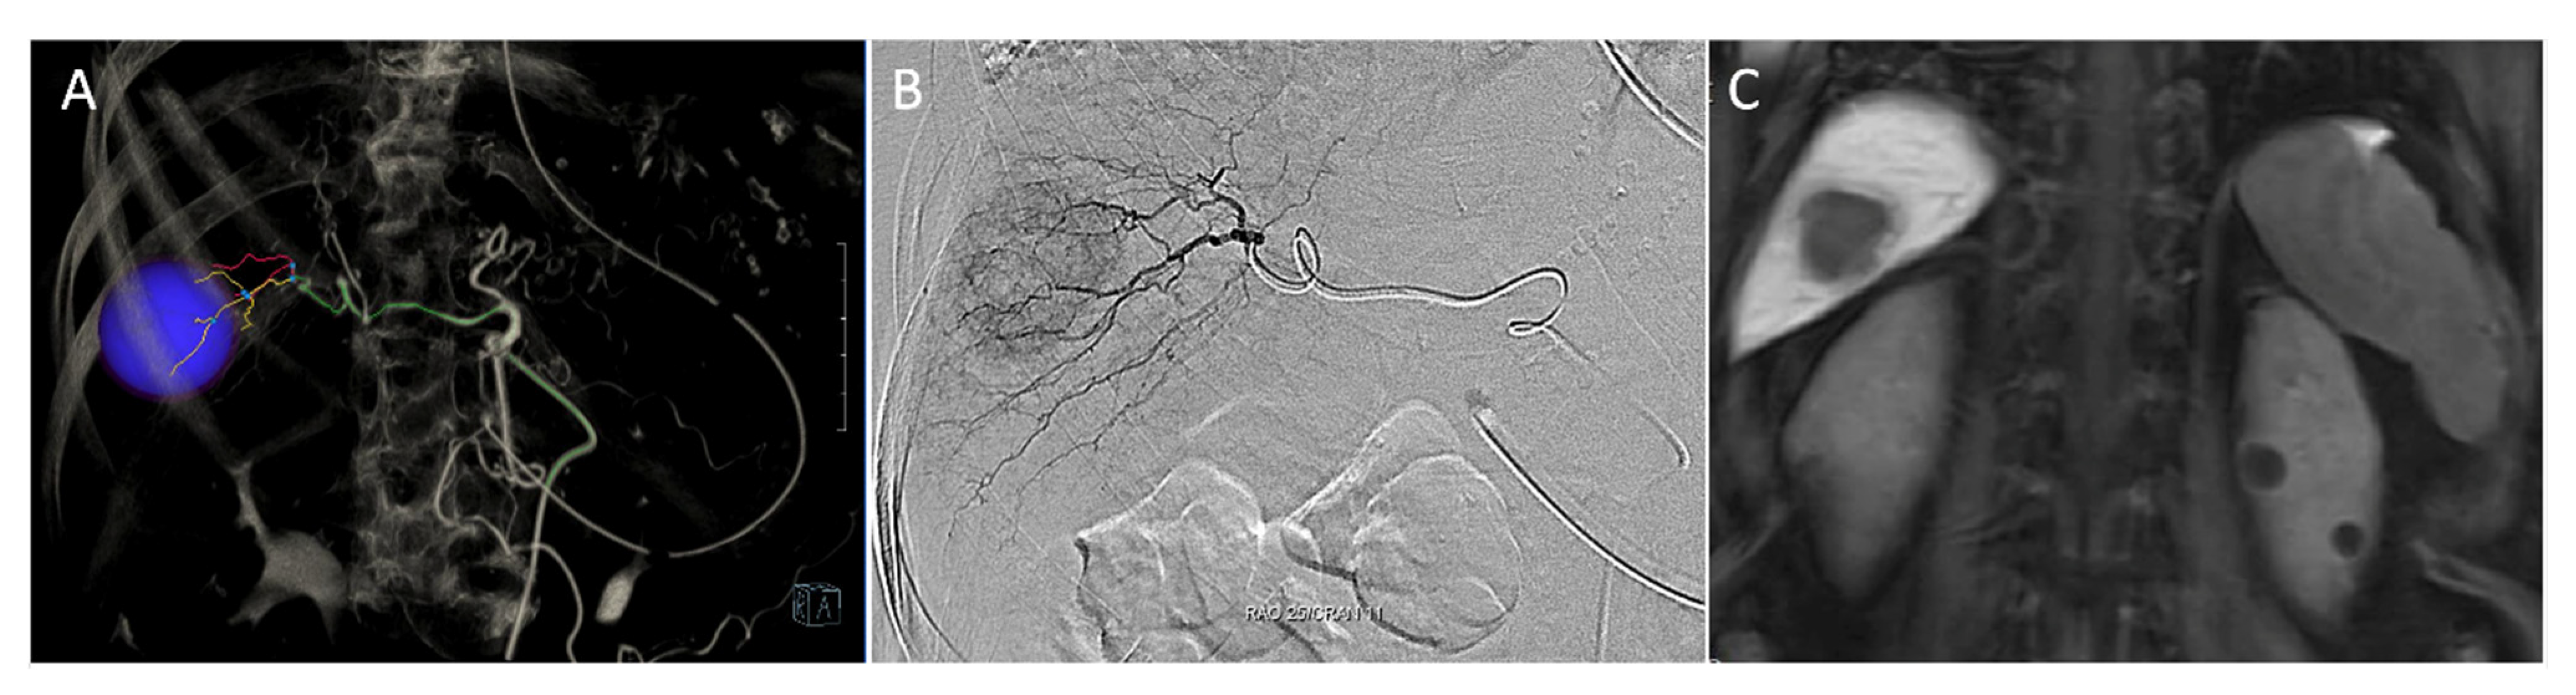

2.1. Detection of Localization under Fluorescent Imaging

2.2. VTLR

- Ueno, M.; Hayami, S.; Sonomura, T.; Tanaka, R.; Kawai, M.; Hirono, S.; Okada, K.I.; Yamaue, H. Indocyanine green fluorescence imaging techniques and interventional radiology during laparoscopic anatomical liver resection (with video). Surg. Endosc. 2018, 32, 1051–1055. [Google Scholar] [CrossRef] [PubMed]